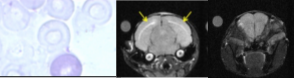

MRI and MRS of experimental cerebral malaria

The overall purpose of this project is to characterize the early pattern of lesion formation with advanced MR methods. We also investigate the sequelae of the cerebral syndrome by an approach ranging from cellular metabolism to brain connectivity.